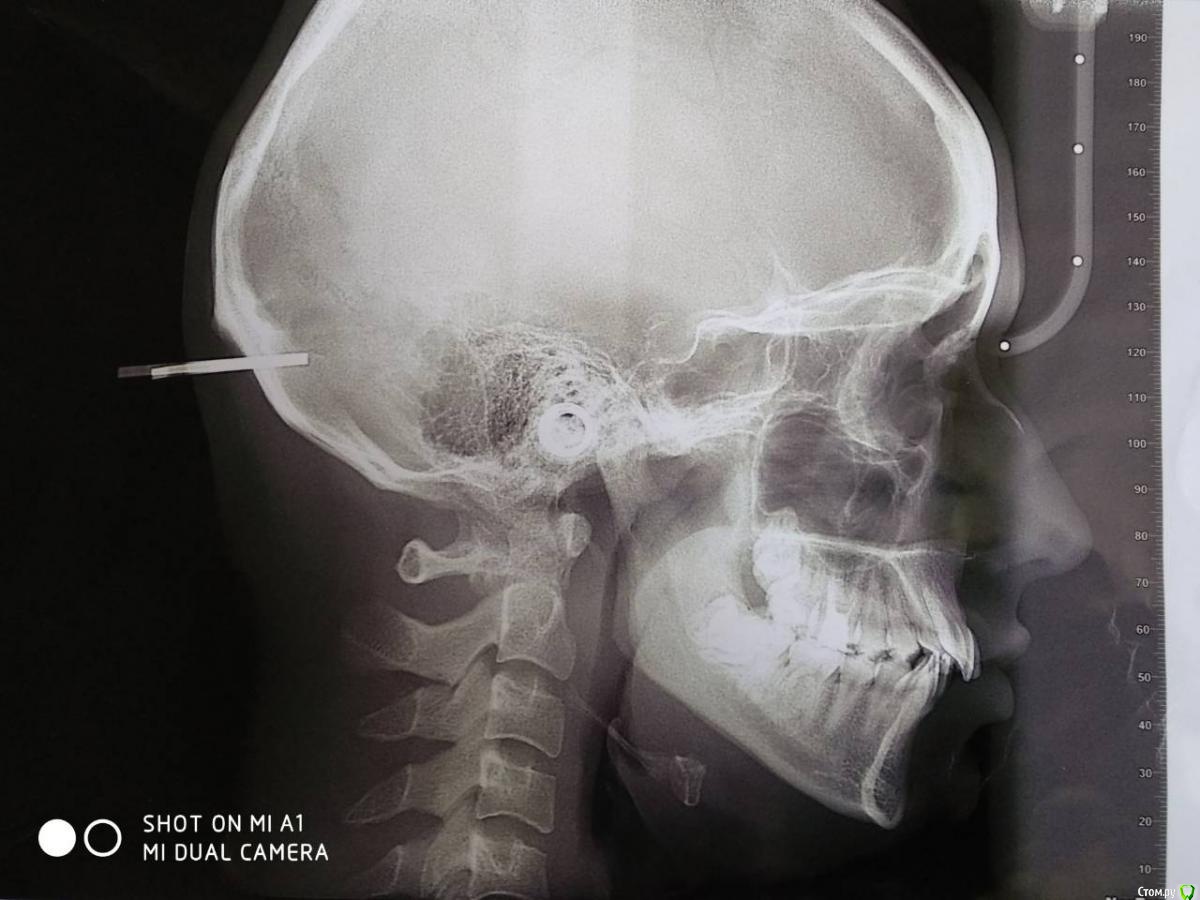

Гелла Опубликовано 23 апреля, 2018 Автор Поделиться Опубликовано 23 апреля, 2018 Здравствуйте, спасибо за ответ.Сейчас удаляем нижние зубы мудрости. Верхние зубы мудрости непосредственно "входят" в гайморовы пазухи, для их удаления требуется сложная челюстно-лицевая операция с ушиванием(?) ходов в гайморовы пазухи.Кроме того, все ортодонты, которые консультирование, настаивали на удалении как минимум двух верхних "четверок".Как, по Вашему мнению, стоит ли сохранение "четверо" столь сложной и малопрогнозируемой операции? Ссылка на комментарий

Monkey Опубликовано 23 апреля, 2018 Поделиться Опубликовано 23 апреля, 2018 Здравствуйте, спасибо за ответ.Сейчас удаляем нижние зубы мудрости. Верхние зубы мудрости непосредственно "входят" в гайморовы пазухи, для их удаления требуется сложная челюстно-лицевая операция с ушиванием(?) ходов в гайморовы пазухи.Кроме того, все ортодонты, которые консультирование, настаивали на удалении как минимум двух верхних "четверок".Как, по Вашему мнению, стоит ли сохранение "четверо" столь сложной и малопрогнозируемой операции?Если не хотите в будущем получить проблемы с височно-нижнечелюстным суставом, то, однозначно, стоит. Главное найти грамотного хирурга. Ссылка на комментарий

DrNice Опубликовано 23 апреля, 2018 Поделиться Опубликовано 23 апреля, 2018 Не вижу проблем, с удалением верхних восьмерок. Ищите адекватного хирурга и будет вам счастье. 1 Ссылка на комментарий